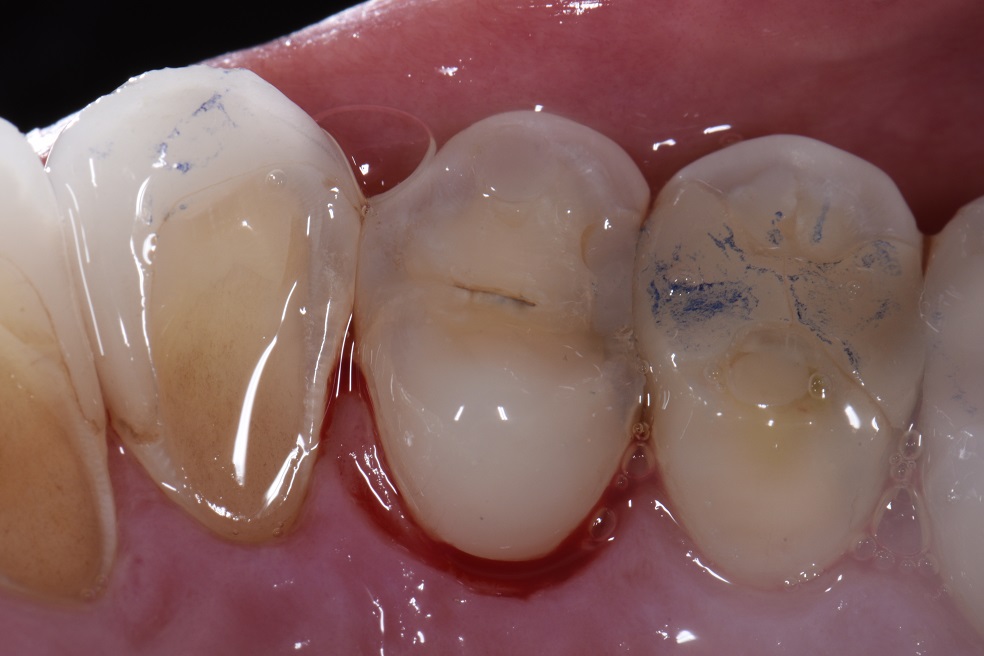

Acid etching (phosphoric acid 37 Ultradent) and application of Does Acid Etching Damage Teeth Acid etching is a procedure used in dentistry when carrying out procedures that require adhesives. teeth etching involves treating the enamel (or dentin) surface of your tooth with an acidic substance (usually a blue gel) to prepare it for bonding with. Just as you might sand. let's go over what etching does to a tooth, the types of. Does Acid Etching Damage Teeth.

Acid etching of the fractured teeth with 37 phosphoric acid (A Does Acid Etching Damage Teeth Acid etching is a procedure used in dentistry when carrying out procedures that require adhesives. does acid etching damage teeth? Just as you might sand. The acid etching does not harm the teeth, but the tooth surface causes demineralization of the enamel. a total of 105 extracted human premolars were divided into six groups regarding the type of. Does Acid Etching Damage Teeth.

Acid etching of abutment teeth Download Scientific Diagram Does Acid Etching Damage Teeth teeth etching involves treating the enamel (or dentin) surface of your tooth with an acidic substance (usually a blue gel) to prepare it for bonding with. The acid etching does not harm the teeth, but the tooth surface causes demineralization of the enamel. When repairing a damaged tooth, one of the biggest challenges is for the filling material to. Does Acid Etching Damage Teeth.